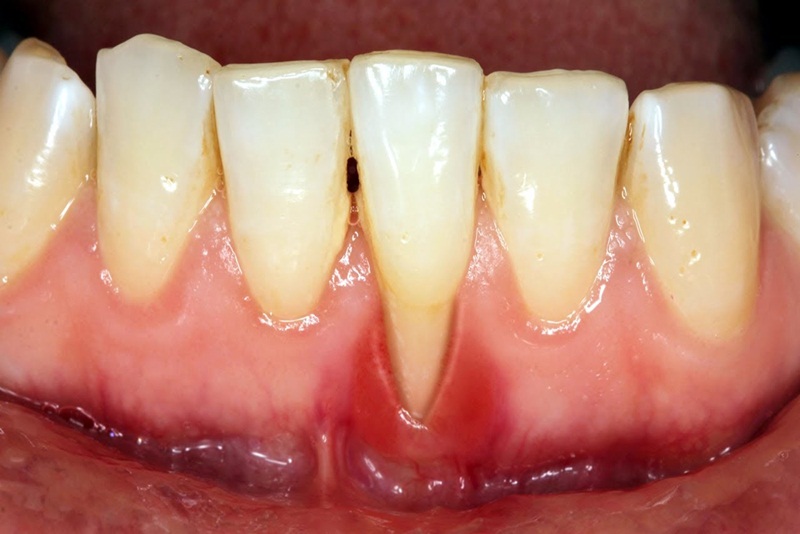

Viêm nướu thường bắt đầu với dấu hiệu là đỏ, sưng và đau ở vùng nướu, khiến cho việc ăn uống trở nên khó khăn và thiếu thoải mái. Đây là tình trạng phổ biến, nhưng nhiều người lại không nhận thức được mức độ nghiêm trọng của nó nếu không được can thiệp kịp thời.

Hình ảnh giới thiệu về tình trạng viêm nướu răng

Một trong những dấu hiệu đầu tiên của viêm nướu là cảm giác đau và sưng tấy tại khu vực nướu. Người bệnh thường cảm thấy khó chịu, đặc biệt khi ăn uống, và có thể thấy nướu có màu đỏ tươi thay vì màu hồng nhạt bình thường.

Dấu hiệu nhận biết viêm nướu là đau và sưng tấy tại khu vực nướu